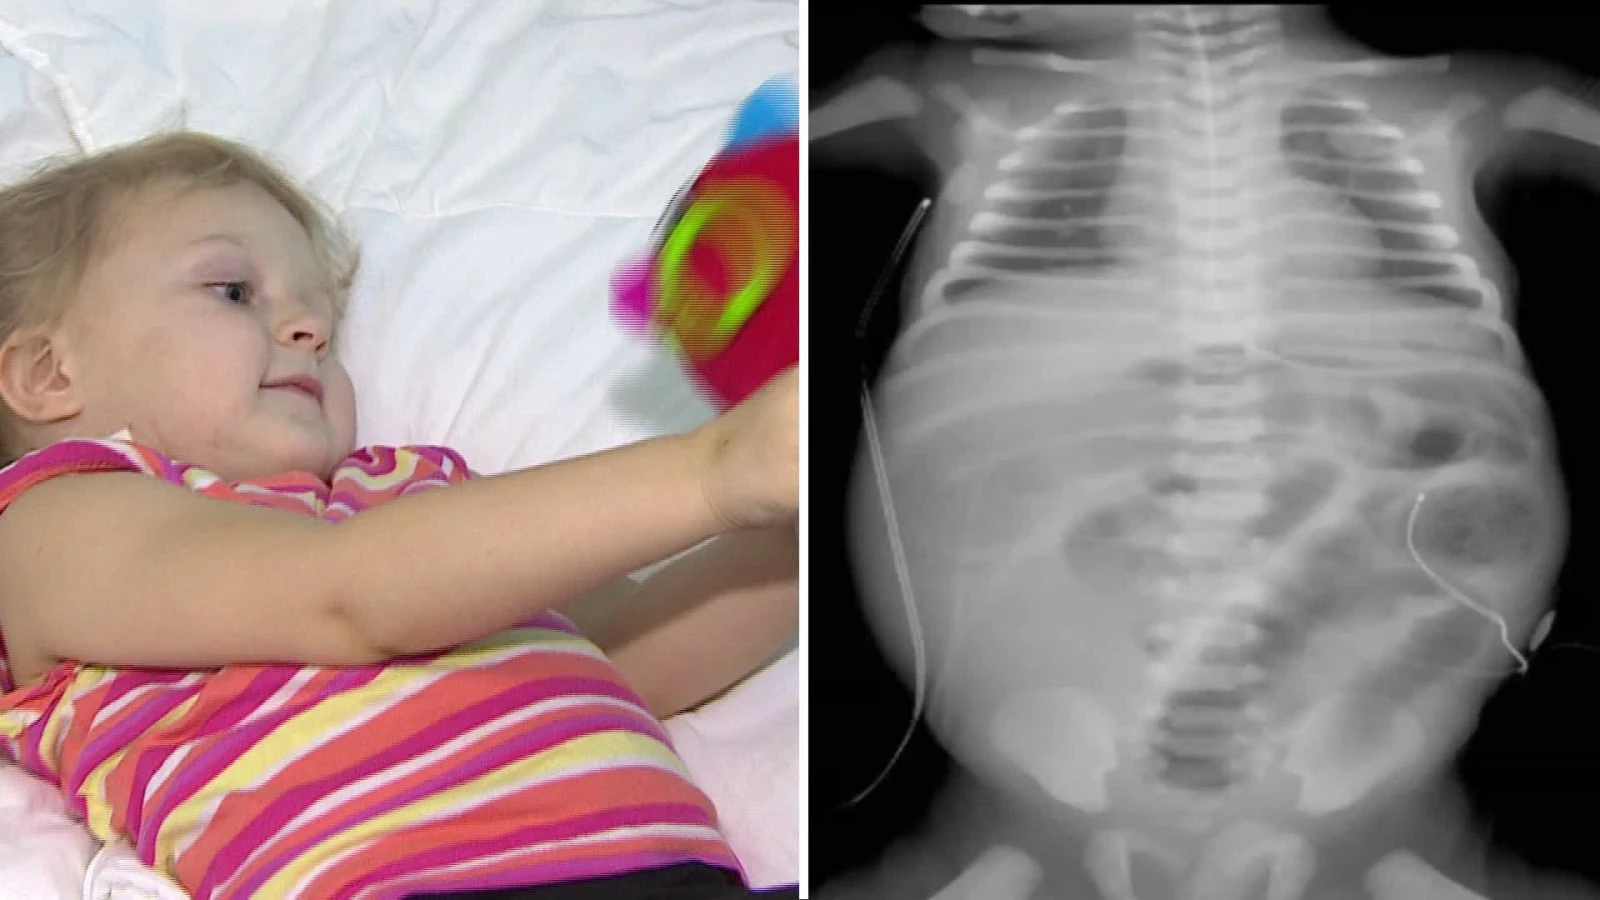

Ukrayna’da yaşayan aile hekimi Dr. Tertısnıy Konstantın, rahatsızlanan eşini muayene etmek için eve ultrason cihazı getirdi. Doktor Konstantın, eşini kontrol ettiği sırada 3,5 yaşındaki Polina isimli kızı yanlarına gelerek kendisinin muayene edilmesini istedi. Küçük kızının ısrarlarını kırmayan doktor baba, minik Polina’nın karnına bakınca gördükleri karşısında şaşkına döndü. Polina’nın karnında tümör olduğunu tespit eden doktor baba, sonuçlardan emin olmak için kızını hemen ülkesindeki bir hastaneye götürerek kontrol ettirdi. Yapılan muayeneler sonrasında küçük kızın karnında tümör olduğu netlik kazandı.

Kızının ısrarı sonucu baktığı ultrasonla hastalığını ortaya çıkaran aile hekimi olan baba Dr. Tertısnıy Konstantın, “Ultrasonla bakınca tümör gördüm. Gördüklerime ilk önce inanamadım. Bir daha baktım yanlıştır diye kızımı hastaneye götürdüm. Ama gerçekti karnında kocaman bir tümör vardı” dedi.

Minik kızın karnında oluşan tümörün sinirleri de içerisine aldığını söyleyen Beyin ve Sinir Cerrahı Prof. Dr. Mustafa Kemal Hamamcıoğlu, “Karın içerisinden omurilik üstüne doğru büyüme yaptığını saptamışlar. Sinirleri de içine alan bir kitlesi vardı. Onu mikroskobik cerrahi ile çıkartıp karın içerisine giren kısmına kadar takip edip işaret koyup o aşamada arkadaşlarıma devrettim” şeklinde konuştu